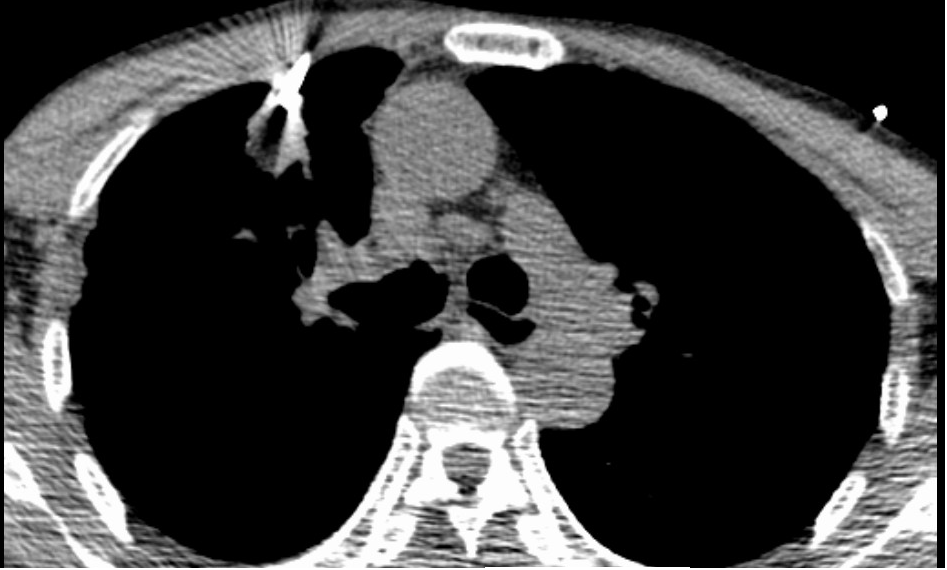

69岁的吴伯(化名)在3年前起出现反复咳嗽、咳痰,症状逐渐加重,并出现胸痛。至我院行胸部CT检查,提示为右肺占位(大小约21mm×19mm),考虑恶性肿瘤的可能性比较大。由于患者年龄较大,肺功能下降,考虑手术创伤较大,恢复较慢,且费用较高,根据患者的情况及要求,专家推荐了风险相对低的消融手术。

经与患者及家属充分沟通后,呼吸与危重症医学科三区为吴伯安排了肺结节微波消融术。术前已行结节活检,病理结果提示为腺癌。手术过程中,在副院长许承琼指导下,通过CT引导定位,布针顺利平稳,布针结束后,随即展开肺结节微波消融术,手术历时不到2小时顺利结束。